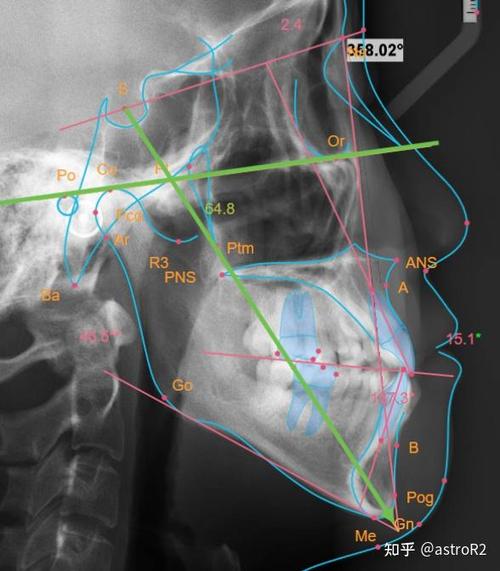

正畸头影测量图的核心价值在于“量化分析”,其通过标志点(如Sella点、Nasion点、A点、B点等)和参考平面(如FH平面、SN平面、PP平面、MP平面等),测量骨骼角度(如ANB角、SN-MP角)、牙齿位置(如U1-NA距、L1-NB距)、软组织形态(如鼻唇角、颏唇沟深度)等关键指标,为医生提供客观依据,在骨性Ⅲ类错颌的诊断中,ANB角<0°且SNB角增大提示下颌发育过度;在拥挤度分析中,通过牙冠宽度与牙弓可用空间的差值,可精准判断是否需要拔牙。

(图片来源网络,侵删) -